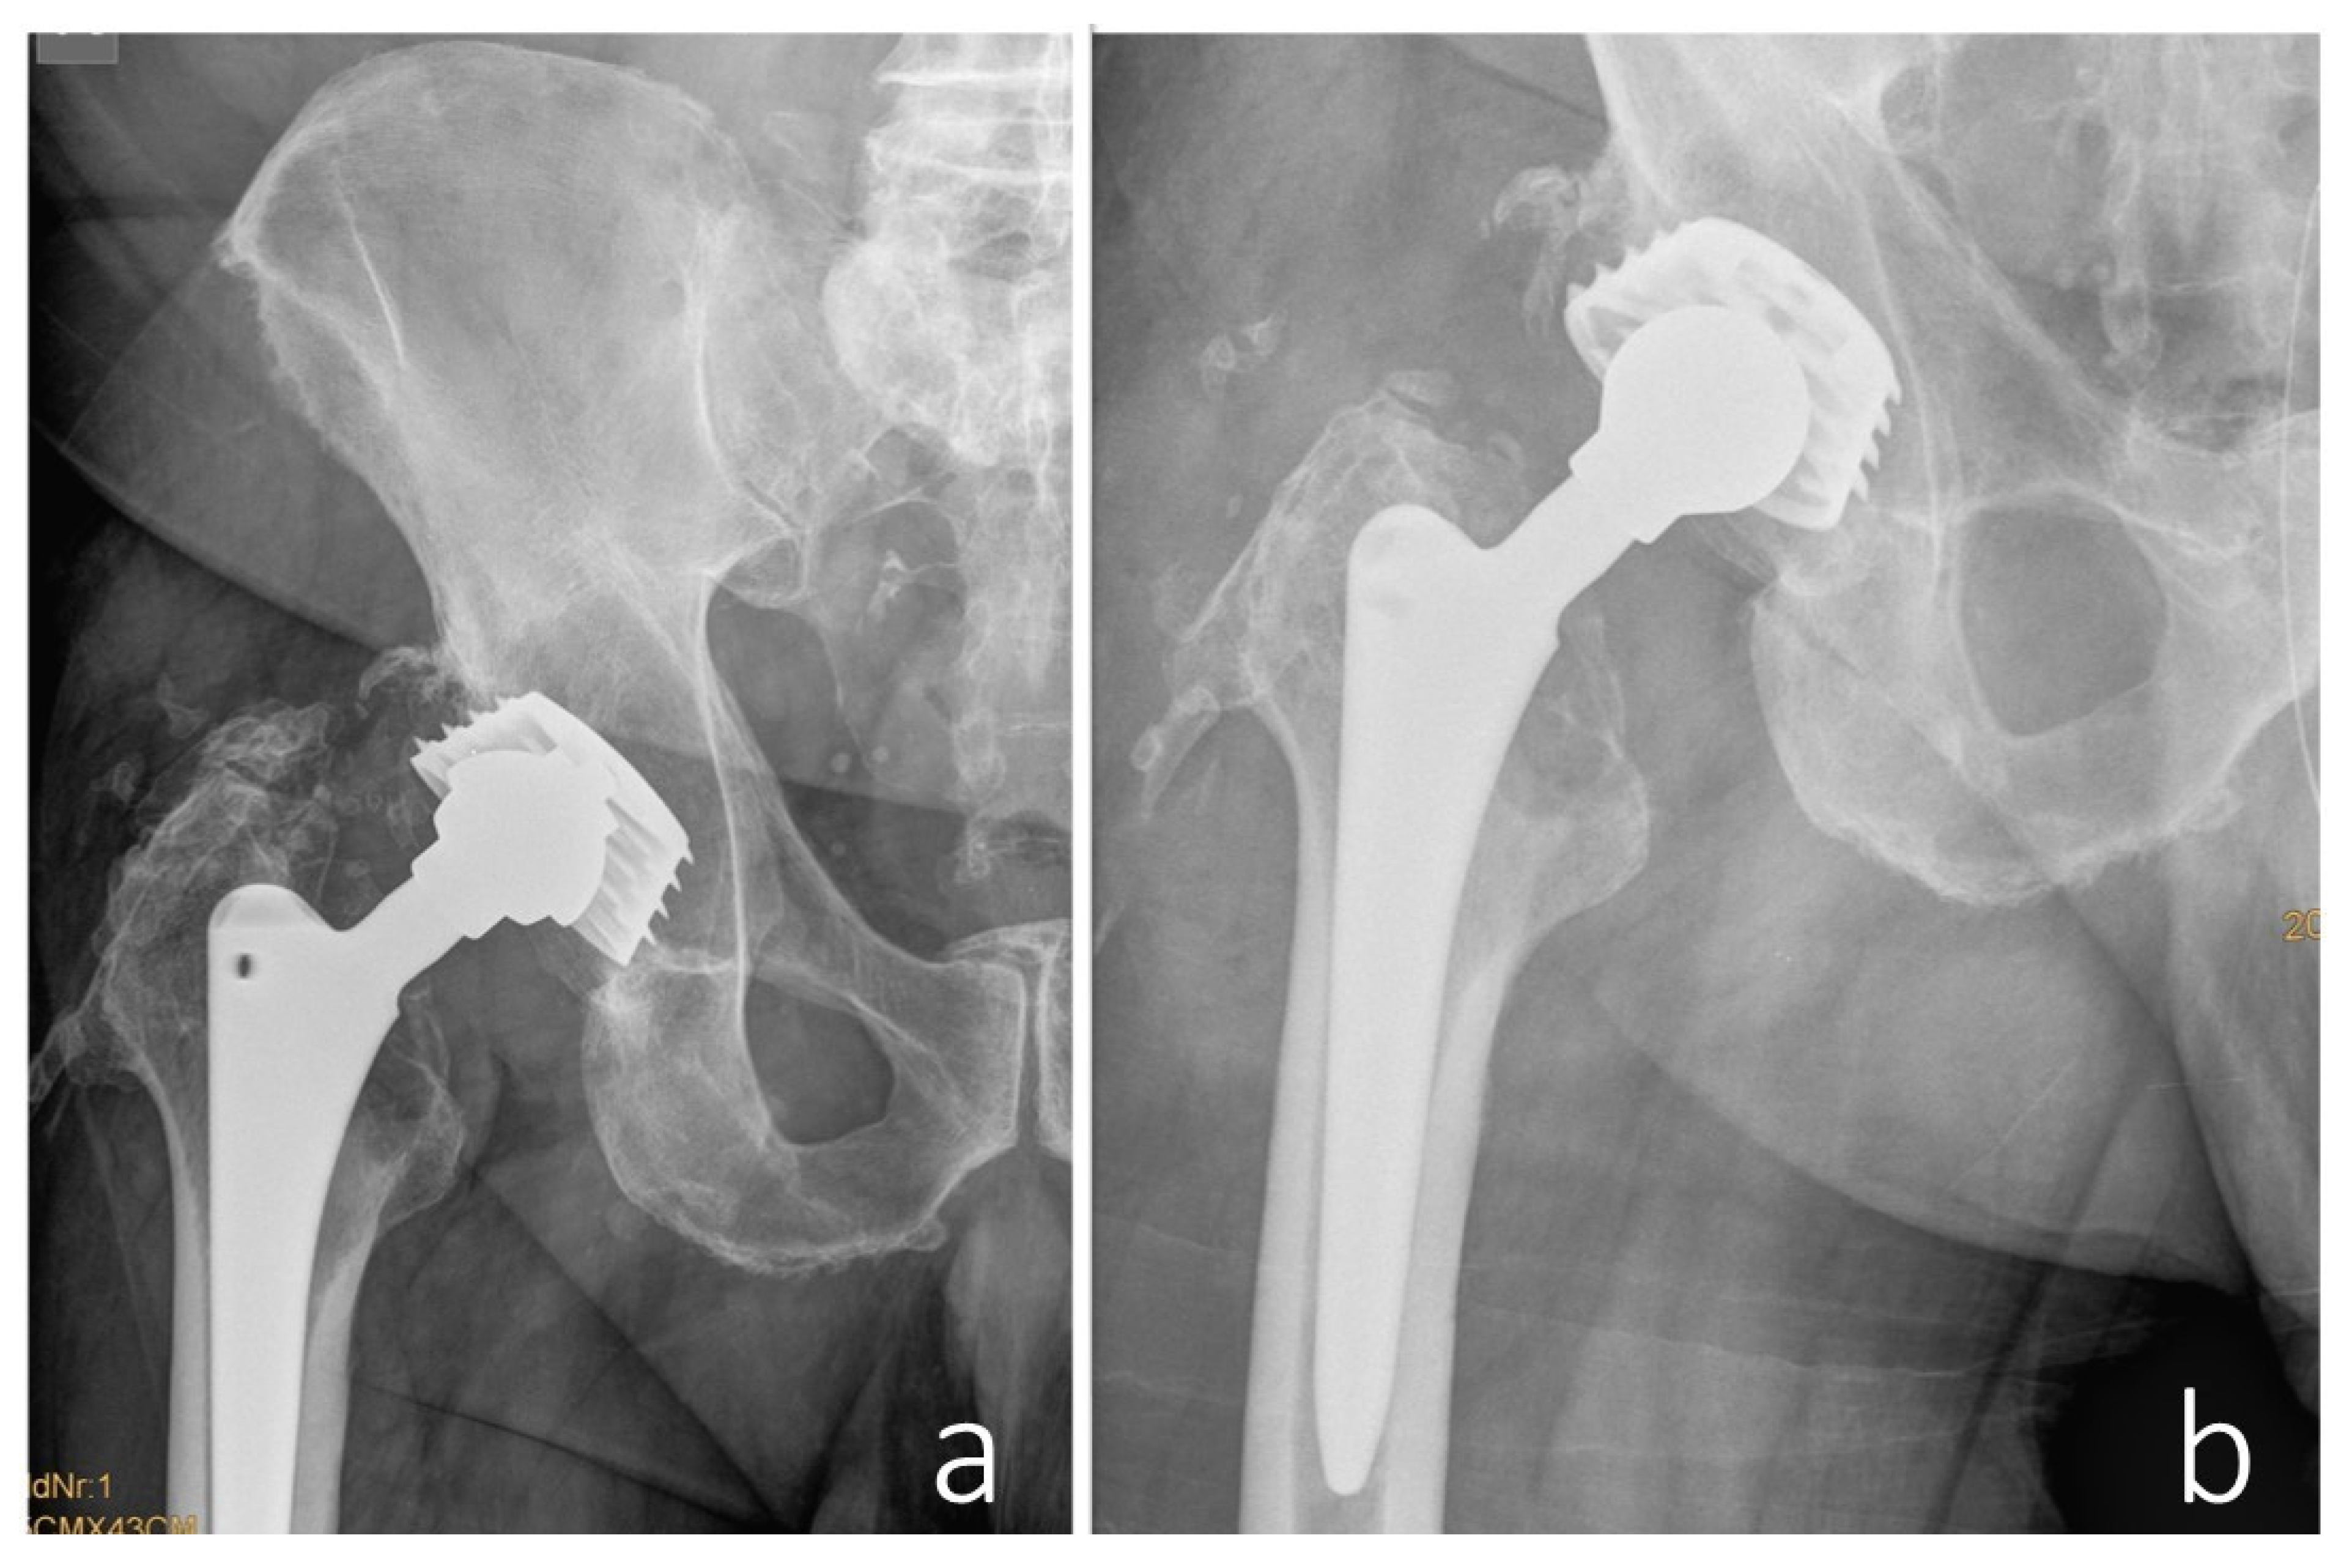

A 75-year-old male patient was transferred to the oncology department of our hospital following the discovery of a large retroperitoneal mass on Computed Tomography (CT) and Magnetic Resonance Imaging (MRI). The lesion, measuring 15 × 13 × 11.5 cm with both cystic and solid components, was adherent to the iliac vessels and suspected to be malignant (Figure 1).

Figure 1. Axial CT (a) and T2-weighted MRI (b) images demonstrate a large, highly heterogeneous retroperitoneal mass in the right pelvis, measuring 15 × 13 × 11.5 cm, with both cystic and solid components and evidence of capsule formation. The lesion displaces adjacent anatomical structures and extends to the infrainguinal portion of the pectineus muscle.